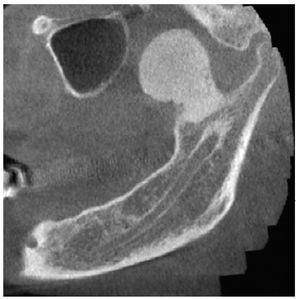

La radiografía panorámica (fig. 1) mostró una estructura de tejido óseo, densa, homogénea, con forma de hongo, bordes bien definidos y un diámetro de varios centímetros. La lesión parecía originarse en un área por encima del agujero mandibular. Un TAC de haz de cono (figs. 2 a 5) reveló la presencia de una lesión homogénea osteodensa de 3 x 3 x 2,7 cm que crecía a partir de un pedúnculo en la cara lingual de la escotadura mandibular. La circunferencia anterior alcanzaba casi a la apófisis coronoides.

Figura 2. Imagen axial de un TAC de haz de cono.